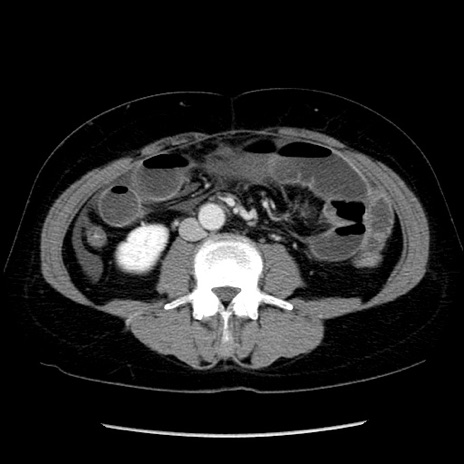

症例6(横断像)

【症例】50歳代女性

【主訴】下腹部痛

【現病歴】本日朝より下痢2回あり。 昼食を食べた後、嘔吐3回、下腹部痛認め、症状軽快せず、当院救急搬送。

最終食事:本日昼(生ものなし)。 昨日の夜、刺身を食ぺたとのこと。周囲に同様の症状の者なし。普段、排便は毎日あるとのこと。

【既往歴】卵巣癌術後(8年前に当院で卵巣摘出)

【身体所見】 意識清明、腹部:平坦、腸蠕動音→、やや硬、下腹部自発痛・圧痛あり、反跳痛あり、筋性防御なし。

【データ】WBC 16000、CRP 0.01